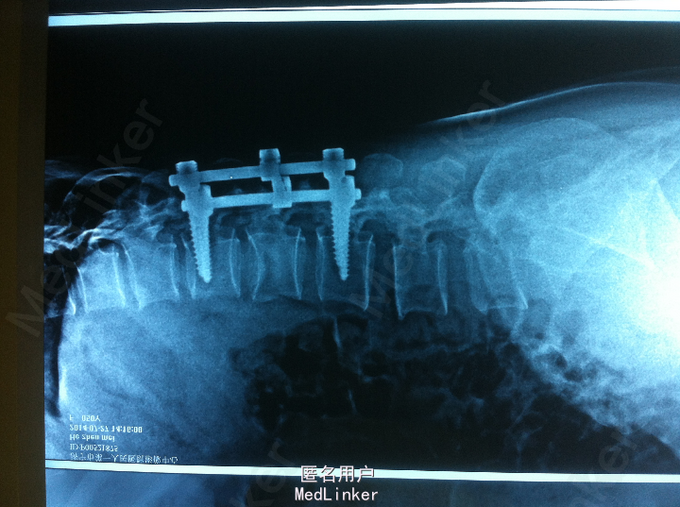

高处摔伤腰部疼痛、活动受限1入院。 中年女性,既往健康; 患者1天前从3米高处摔伤,臀部着地,及感腰部疼痛、活动受限,双下肢无放射性疼痛、麻木,双下肢活动可。

PE:腰部轻度后凸,叩痛,双下肢感觉无减退,双下肢肌力4-5级,巴氏征 阴性。 X-ray:腰2椎体骨折 CT:腰2椎体骨折,椎体后缘不连续 MR:腰2椎体骨折,腰2-3椎体水平硬膜外血肿

诊断:腰椎骨折 腰椎硬膜外血肿 处理:腰椎后路撑开复位内固定

术后1个月,患者轻度腰痛,双下肢感觉无减退,双下肢肌力5级 术后3个月,患者无明显腰痛,双下肢感觉、肌力正常 讨论:1、腰椎骨折累及中柱,无神经损伤表现,是否必须行椎板减压 2、外伤性硬膜外血肿,无神经损伤表现,是否有椎板减压指征